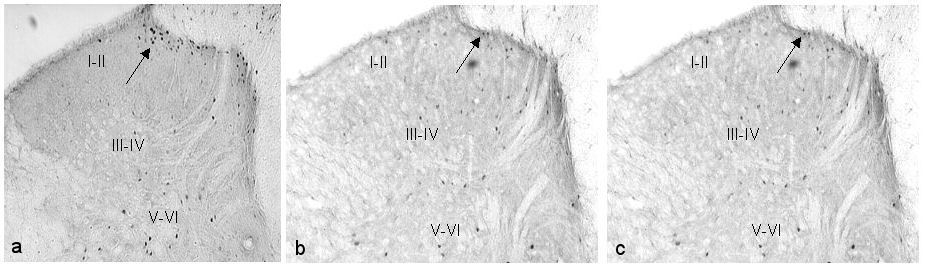

FLI

In the non-stressed animals given formalin, the highest density of FLI expression can be seen in the saline group, concentrated mainly on the ipsilateral side. In the morphine and ketamine groups, there were reductions in FLI expression (Figure 3 [Fig. 3]).

All stressed groups showed FLI expression on both the ipsilateral and contralateral sides. However, the distribution of the FLI in ipsilateral laminae I–II was more scattered compared with the non-stressed groups which concentrated mainly over the medial aspect of the laminae. Among the three groups, ketamine stressed group demonstrated the highest FLI expression on both the ipsilateral and contralateral sides of the spinal cord (Figure 4 [Fig. 4]).